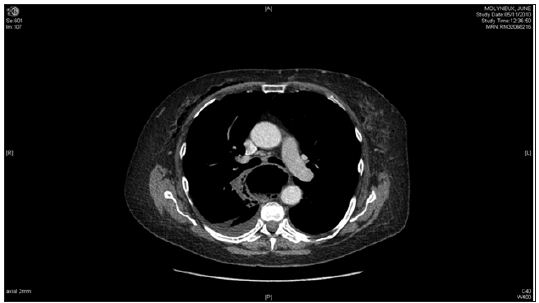

60-year old female with symptoms of dysphagia and reflux underwent diagnostic oesophago-gastroduodenoscopy (OGD). Immediately post-procedure, patient complained of chest pain and shortness of breath. Surgical emphysema was present in the neck and Computed Tomography (CT) confirmed oesophageal perforation in an upper oesophageal diverticulum (Figure 1). She remained well whilst managemened conservatively for 10 days with nasogastric tube, intravenous antibiotics and omeprazole. Subsequently the patient became septic, developing signs of mediastinitis and lung consolidation. She was transferred to Intensive care unit (ICU) where parenteral nutrition was commenced and antibiotics were changed appropriately. A repeat CT did not demonstrate any collections which required drainage, however there was a large iatrogenic oesophageal diverticulum extending from the retropharyngeal space down to the posterior mediastinum, just beyond the carina, compressing on the oesophagus. The patient also developed a neck swelling and air leak from a suspected perforated pharyngeal pouch for which ENT opinion was sought.

Figure 1: